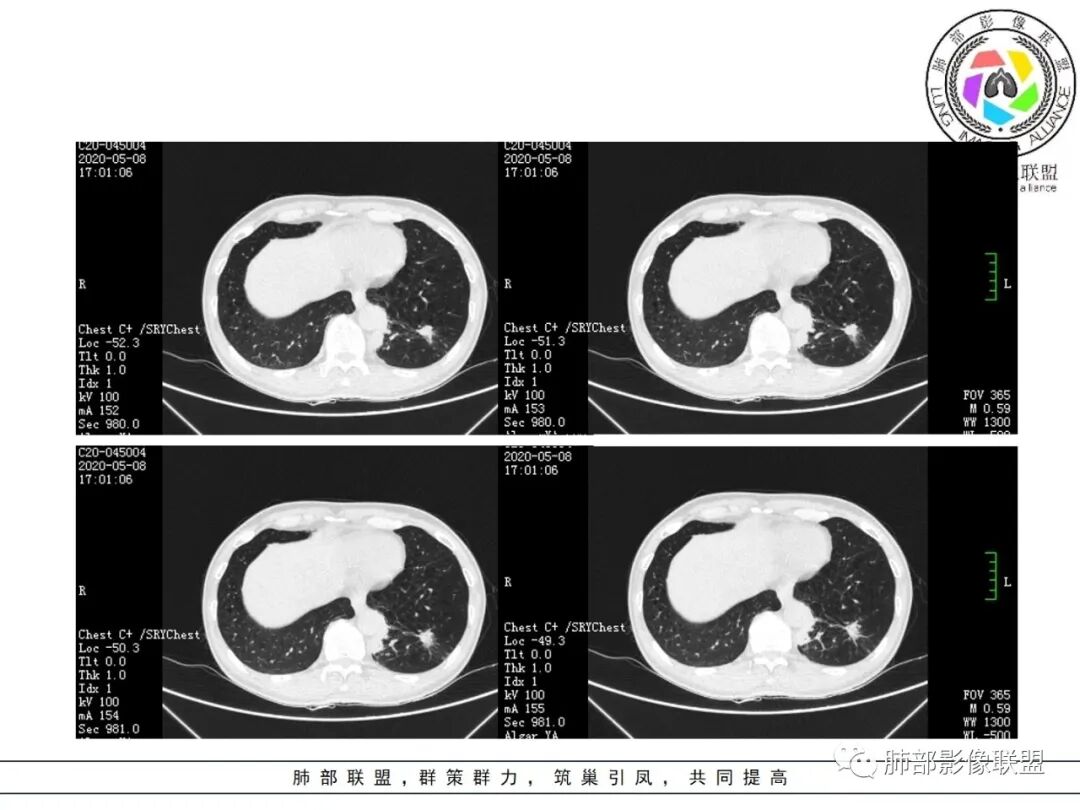

大雄:抗感染不吸收还是要警惕癌尤其主动脉旁的病灶红星:老年患者,咳嗽咳痰两个月,既往有糖尿病病史10年,左肺下叶后基底段斑片状、条索状、斑点状多形态的病灶,病灶内可见支气管征以及狭窄扩张的支气管影像。重建图像上可见到病灶沿支气管爬行。增强扫描病灶轻度强化,临近胸膜增厚。首先考虑感染性的病变,结核性的可能性最大。鉴别诊断上注意排除肺克以及淋巴瘤。三个石头:左肺下叶多发斑片,结节,条索,多态性?结核?多个结节边缘长毛刺,胸膜牵拉,分叶。矢状位支气管走行扭曲,没有完全阻塞,应该有粘液栓,有点像指状。主动脉旁病灶边缘平直,部分有鹏隆感,延迟强化。抗炎病灶变化不明显,结核?真菌?肿瘤也除外不了。没意见:左肺下叶基底段结节,膨隆、深分叶,毛刺,内侧串珠结节,中轴间质增厚,管腔狭窄,后基底段亚支不张,强化情况不明,考虑恶性,腺癌可能性大,另指套样征像,支气管壁增厚,不除外霉菌感染流心明智:老年患者,咳嗽咳痰2月。既往糖尿病史10年。胸CT:左肺下叶基底段多发结节影、斑片影、条索影,多数结节影沿支气管血管束分布,支气管壁厚,部分结节分叶、指状突,后基底段支气管狭窄闭塞。重建可见到病灶沿支气管爬行。增强扫描病灶明显强化,部分斑片影内可见低密度灶。普通抗感染无效。考虑:恶性病变,鳞?小?鉴别TB、隐球等。王秀仙:左肺下叶沿支气管血管束分布斑片、结节影,部分呈管状铸型生长,管腔狭窄,后基底段支气管阻塞,降主动脉旁不张实变,增强扫描病灶轻度强化,抗感染2周无吸收,考虑鳞癌。鉴别结核。蓝天白云:肺野内老年男性,咳嗽咳痰,有糖尿病病史,抗炎治疗无吸收。影像表现为左肺下叶支气管腔内结节影,支气管壁增厚,远侧小花小草,增强后实变影均匀强化,考虑鳞癌伴远端阻塞性炎症,鉴别结核。采莲:老年男性,咳嗽咳痰2月,有糖尿病史,左肺下叶沿支气管分布多发结节条状影,结节影不规则有分叶,成串珠样,靠下结节影成条索影,周围有空气储留,靠近主动脉不规则块状影,边缘平直,周围支气管壁增厚,支气管进入后阻塞,有糖尿病史,首选考虑炎性肺结核可能性大,鉴别肺鳞癌。了:左肺多发结节影,实性结节,,磨玻璃结节,左肺门结节影,深分叶,彭隆感,有血管滋养,考虑肿瘤,抗感染后病灶无吸收,感染不像,结节有强化,无卫星灶,结核可以排除不再涩的柠檬:老年男性,吸烟史,糖尿病史,咳嗽咳痰2月,抗感染2周无效。左下基底干及各分支管壁较弥漫增厚,伴支气管粘液栓,远端阻塞性肺炎,后基底段部分不张实变。先考虑感染病变,常规抗炎无效,需考虑结核、曲霉等,不能排除鳞癌合并感染,建议支气管镜检查。

斑片影,考虑阻塞性炎症。

1.关于病灶分布:本例多发小片影局限在左肺下叶,其他肺叶未见异常病灶。

2.关于支气管:上述病灶辖区外侧段支气管截断,环壁结节,远端阻塞性肺炎,是肺癌的重要征象。

3.关于胸膜增厚:本例未见明显的胸膜凹陷及牵拉。病灶较小价值收缩力不强,同时因鳞癌的破坏力强,也抵消了肿块本身的收缩力。